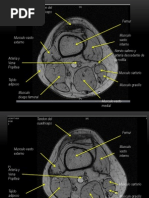

Figura 4. Secuencia spin echo potenciada en T1. Las estructuras con tiempos de relajacin muy cortos, como el de la grasa intraconal de la rbita, se observa con una seal alta (gura 4a). La sustancia blanca, por ser rica en grasa, tiene tambin una seal alta. Las sustancias con tiempos de relajacin ms prolongados, como el agua, se ven de muy baja seal; por ejemplo, el lquido cefalorraqudeo y la sustancia gris que son estructuras ricas en agua (gura 4b).